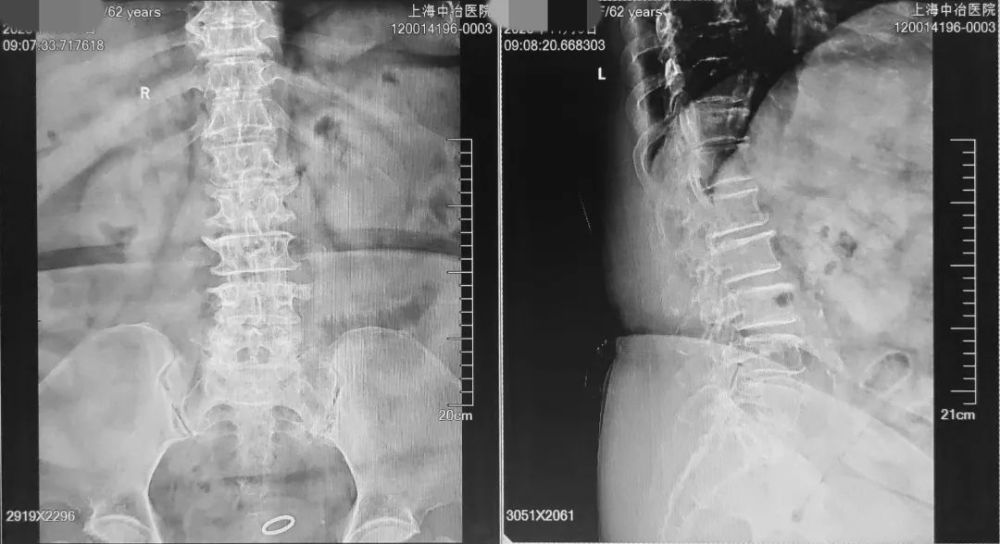

X线

在发育性或混合性椎管狭窄者 , 主要表现为椎管矢状径小 , 椎板、关节突及椎弓根异常肥厚 , 两侧小关节移向中线 , 椎板间隙窄;退变者有明显的骨增生 。 在侧位片上可测量椎管矢状径,14mm以下者示椎管狭窄 , 14~16mm者为相对狭窄 , 在附加因素下可出现症状 , 也可用椎管与椎体的比值来判定是否狭窄 。

文章插图